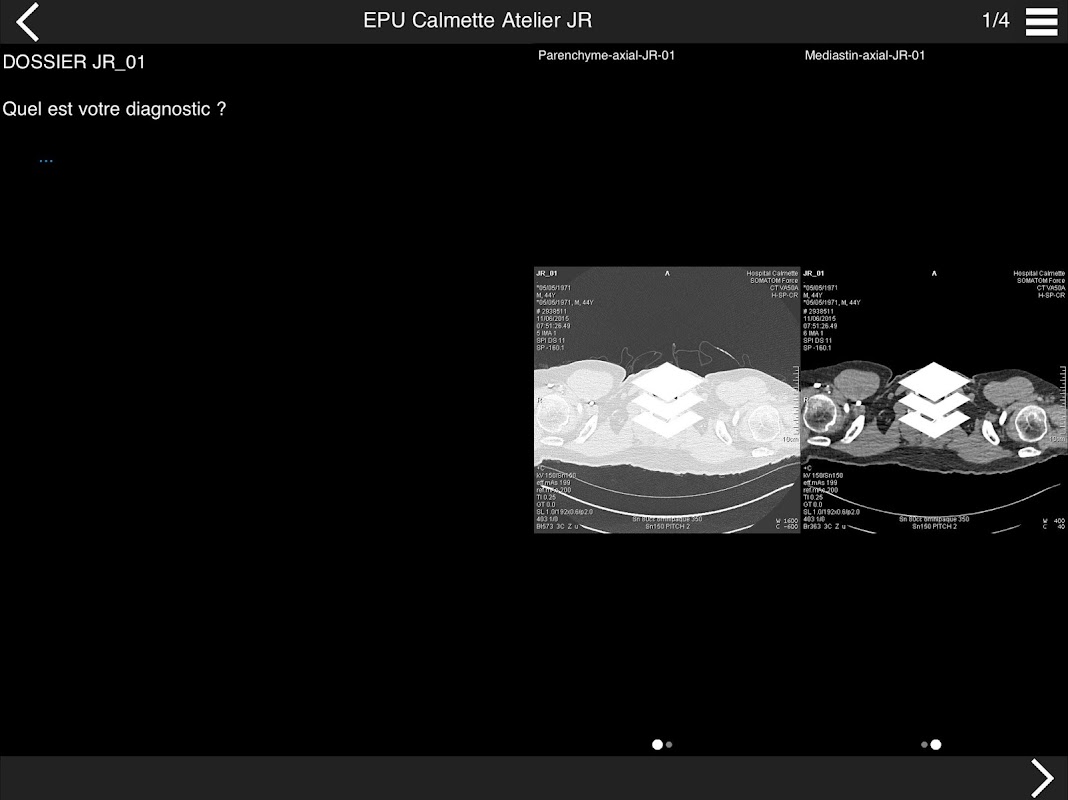

Retrouvez les cas cliniques du Cours intensif de TDM multicoupe du thorax dans cette application.

Thèmes du cours 2017 :

ACTUALISATION DES PROTOCOLES

• DE LA SéMIOLOGIE AU COMPTE-RENDU

* BPCO et nodules pulmonaires : recommandations en 2017

* Pathologie interstitielle : lésions élémentaires et « patterns »

* Pathologie vasculaire et médiastinale

* Oncologie thoracique : bilan standard et introduction à l’étude de l’angiogénèse

* Amiante : images pièges et discordances des secondes lectures.

• INITIATION A L’IMAGERIE CARDIO-THORACIQUE INTEGRéE

* La pathologie que l’on ne peut plus méconnaitre dans le cœur sur un examen

thoracique

Pr J. REMY - Pr M. REMY-JARDIN

Dr J.B. FAIVRE - Dr F. PONTANA

Hôpital Calmette - CHRU de LILLE